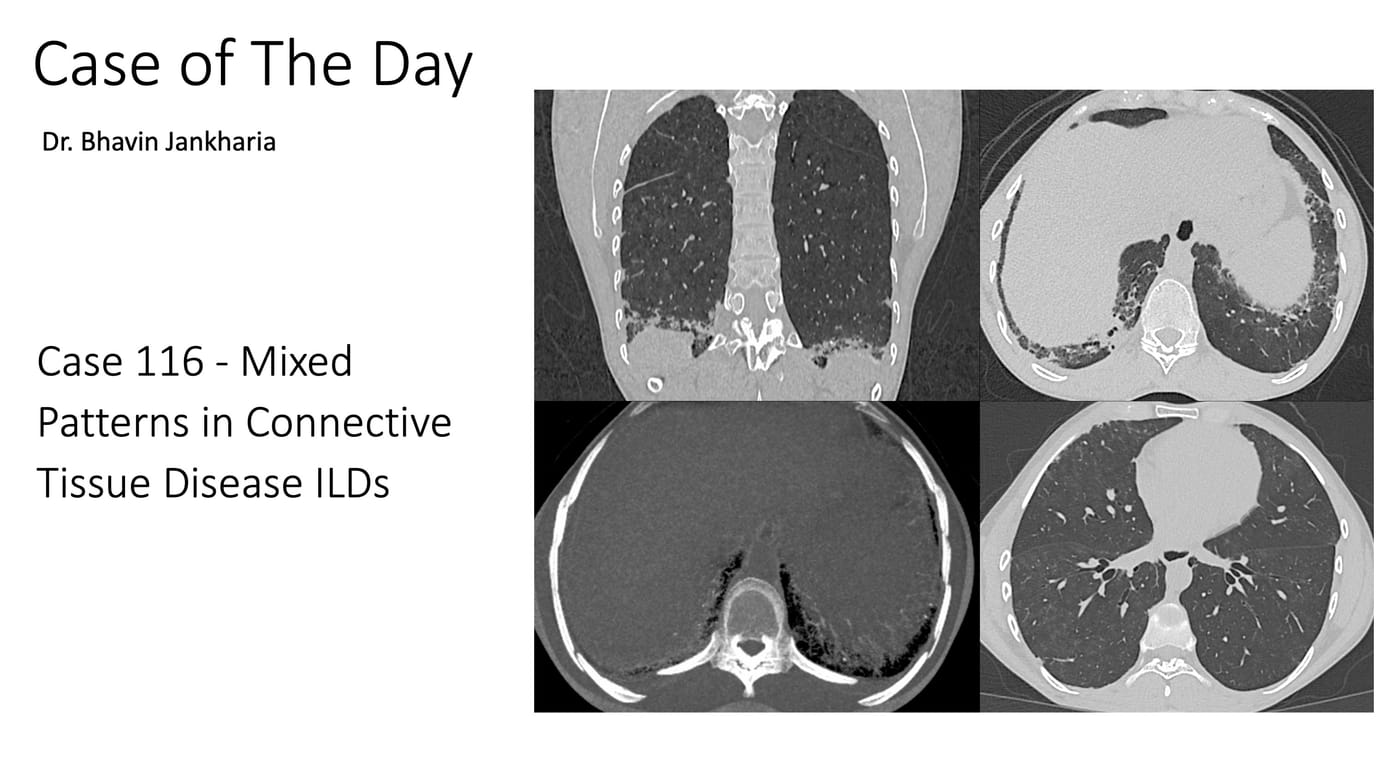

Case of the Day 116 - Mixed Patterns in Connective Tissue Disease ILDs Paid Members Public

Mixed patterns are increasingly being recognized in CTD ILDs and should be mentioned in the report.